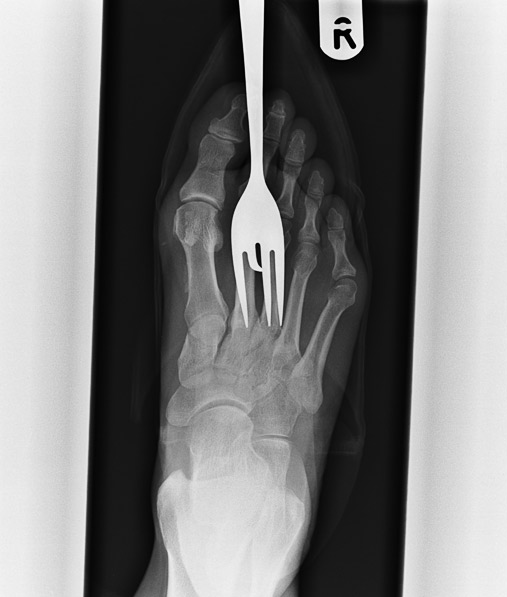

6) Sin palabras… Así luce un pie “atacado” por un tenedor suelto en la cocina. ¡Que no te pase!

Barcroft | The Telegraph